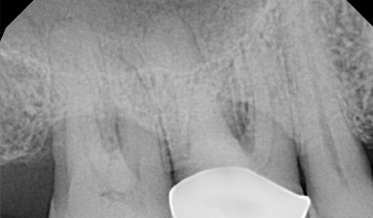

Use of Tuberosity Tissue Block for Tunneling Reconstruction of Class III Sockets With Simultaneous Implant Placement: A Case Report